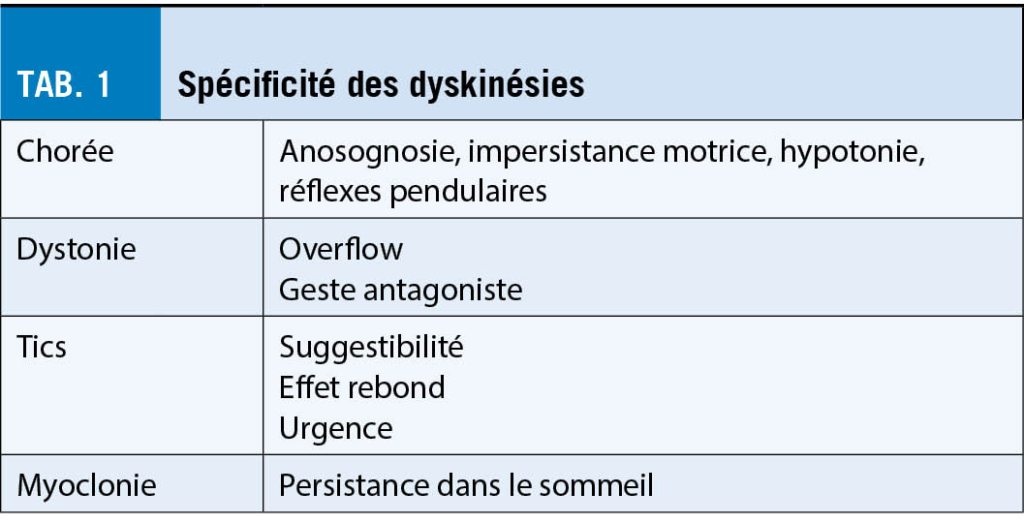

Les dyskinésies oro-facio-masticatrices sont les mouvements anormaux les plus souvent rencontrés après le tremblement postural chez le patient âgé. Fréquentes chez les édentés, elles sont quasi ubiquitaires chez les patients encore sous neuroleptiques de première génération. Les formes stéréotypées et les formes dystoniques sont les plus fréquentes, parfois très grossières avec protrusion de la langue. Ces dyskinésies répondent généralement bien aux neuroleptiques atypiques comme la quétiapine ou la clozapine. Les traitements anticholinergiques sont contre-indiqués, pouvant aggraver des troubles cognitifs chez le patient âgé. Le tableau 1 résume les spécificités des dyskinésies.

La chorée consiste en des mouvements brefs, rapides, sans but, de flexion-extension rotation ou croisement rapides, fluents le long des membres de façon proximo-distale ou vice-versa, et sur la face mimant des tics, augmentant au stress et à l’ action, dont le patient est anosognosique ou qu’ il camoufle. Les signes spécifiquement associés à rechercher sont l’ hypotonie, des réflexes pendulaires, une impersistance motrice (impossibilité à maintenir une posture ou un mouvement fixe, «milk man sign» en serrant la main).

Une dystonie, soit une co-contraction durable des muscles agonistes et antagonistes engendrant des postures anormales associées à des mouvements anormaux (tremor brusque, myoclonies, athétose…) peuvent se voir surtout au niveau axial cervical, rachidien ou des membres, voire du visage. Les signes spécifiques sont le geste antagoniste qui la fait disparaître momentanément, l’ overflow (diffusion aux zones proches). Étant des pathologies génétiques ou lésionnelles, les dystonies se rencontrent plutôt chez le jeune à l’ exception du syndrome cortico-basal. L’ hémispasme facial, classé dans les dystonies, n’ en n’ est pas vraiment une. Ce sont des contractions toniques ou rythmiques intermittentes synchrones sur la branche supérieure et inférieure du nerf facial, la cause est soit compressive (boucle vasculaire), post paralysie faciale ou sans cause évidente. Comme le blépharospasme, il répond très bien à la toxine botulique, les cas graves ou résistants peuvent répondre à la chirurgie décompressive microvasculaire. Le traitement de choix des dystonies est la toxine botulique et dans les cas graves ou résistants, la stimulation pallidale.

Les tics ont généralement disparu chez la personne âgée, sauf peut-être pour les formes très rares tardives sur neuroleptiques ou post AVC. Ils peuvent être moteurs, sensitifs, psychiques, cloniques, toniques, simples ou complexes. La plupart sont héréditaires, les formes postencéphalitiques, post-traumatiques ou postanoxiques sont rares. Leurs signes spécifiques sont le rebond après demande d’ arrêt complet de tout mouvement pendant 1 minute, la suggestibilité qui les fait apparaître, et la sensation d’ urgence si on les empêche. Les neuroleptiques (aripiprazole, tiapride, clozapine, olanzapine) sont en principe efficaces, les formes graves peuvent répondre à la stimulation pallidale.

Les myoclonies sont de brèves contractions (myoclonies positives) ou une perte soudaine de tonus musculaire (myoclonies négatives, astérixis ou flapping tremor), non suppressibles et persistant dans le sommeil. Elles peuvent être spontanées, à l’ action, en réponse à une stimulation sensitive, focales et multifocales. Il convient d’ exclure en premier lieu une pathologie métabolique ou toxique surtout si les myoclonies sont associées à un état confusionnel. Elles sont de mauvais pronostic en présence de troubles cognitifs progressifs : on les rencontre dans les variantes rapides de maladie à corps de Lewy, d’ Alzheimer ou de Creutzfeldt-Jakob, plus rarement dans une maladie auto-immune. Le clonazépam et le lévétiracétam sont les médicaments de choix.